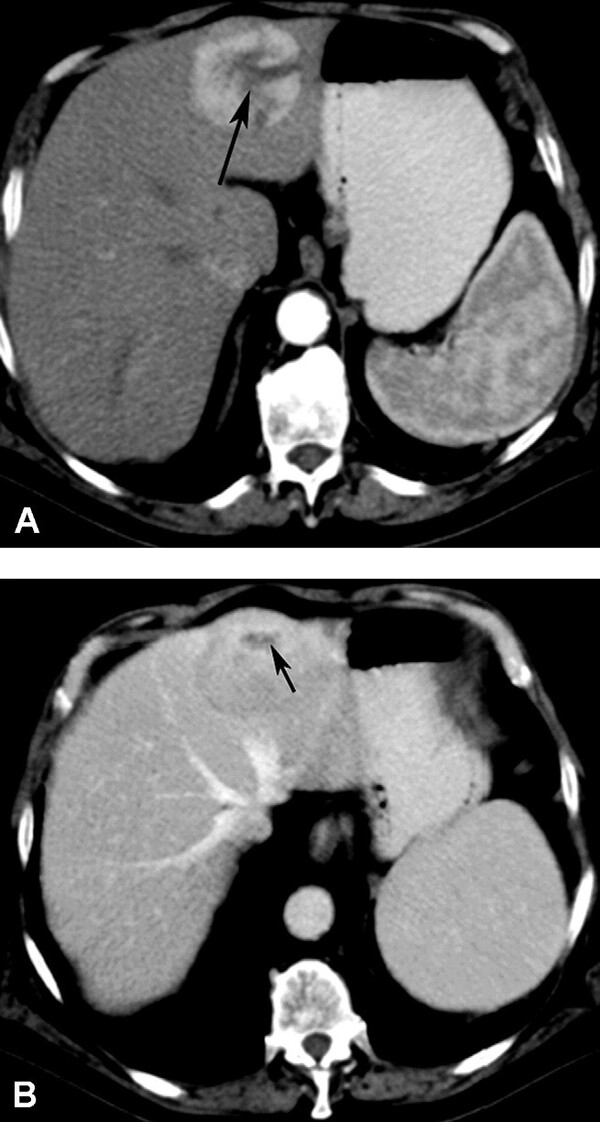

Sự di trú mảnh lách vào trong gan (intrahepatic splenosis) là một tổn thương hiếm gặp biểu hiện là khối trong gan giàu mạch máu ở bệnh nhân sau phẫu thuật cắt lách. Nói chung, nó là tổn thương khu trú một hoặc nhiều ổ, giới hạn rõ, bắt quang mạnh và đồng nhất ở thì động mạch trên CT hoặc MRI, thải thuốc ở thì tĩnh mạch cửa (Hình 21). Các tổn thương đồng tín hiệu với gan trên T1W và tăng tín hiệu so với gan trên T2W. Sự di trú mảnh lách vào trong gan có thể cho thấy ngấm technetium sulfur colloid trên chụp xạ hình nhấp nháy hoặc ngấm SPIO trên MRI.

Hình 21. Nam 28 tuổi có di trú mảnh lá ch vào trong gan sau khi cắt lách. CT không cản quang (A) thấy các khối từ đồng đến giảm đậm độ (mũi tên) ở gan. Các khối bắt thuốc (mũi tên) ở thì động mạch (B) và thải thuốc (mũi tên) ở thì tĩnh mạch cửa (C). Dạng bắt quang tương tự như lách. Sinh thiết là mô lách.